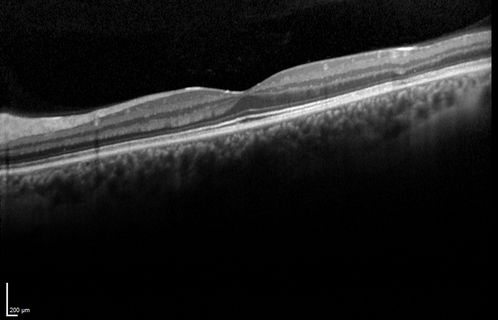

Acute Posterior Multifocal Placoid Pigment Epitheliopathy - 4 years after onset

4 years after presentation - vision 20/80 OD 20/16 OS and there is subretinal fibrosis